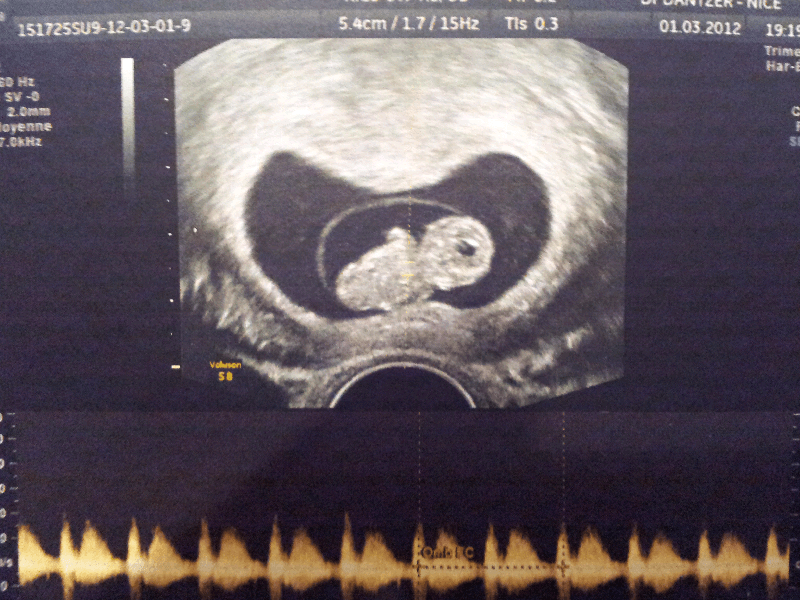

Et voila mes echos d'hier a 9SA +2jours!!

C'etait incroyable!!un mini bébé de 2cm et demie!

On a pu entendre son coeur le voir battre.

Il m'a meme fait une echo 3D!!! C'etait hallucinant!!on voyait ses petit doigts,ses pieds et son visage trop trop beau!!!Mais j'ai pas eu les images:-(

Tout va bien!!